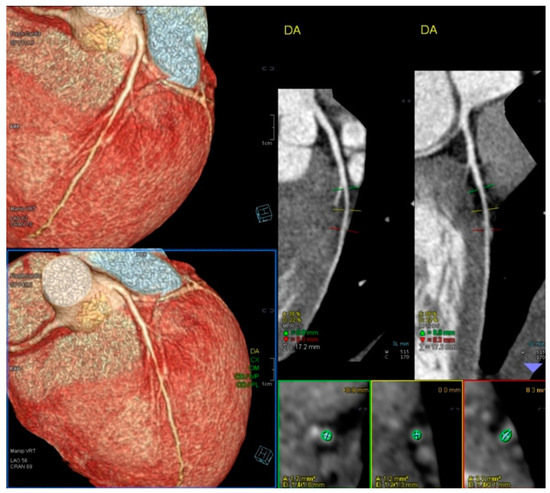

A comparison between the two groups defined by the variable IVG was performed by employing Welch’s test for two independent samples because the sample sizes were unequal. The size of our sample allows us to resort to the central limit theorem, implying that we do not have to verify the normality of the distributions. In Group I, children who developed IVG attained a greater heart rate (HR) of 184 ± 12 vs. 174 ± 16 (p < 0.001) and a higher systolic blood pressure (BP) of 150 ± 19 mmHg vs. 136 ± 23 mmHg (p < 0.001). To compare the odds of reproducing symptoms across the groups defined by IVG, we performed a logistic regression, where the response variable was “Reproduce Symptoms”, and the independent variable was IVG. The OR of exercise stress echocardiography to reproduce the symptoms these children had when comparing the 101 children with IVG with the 158 without IVG was 8.22 ((4.84–13.99) p < 0.001 (95% CI)). One of the children who suffered from chest pain and syncope related to intense exercise had an increase in troponin, but both their coronary angiography and CCTA were normal (Figure 4). After those exams, an ESE was performed, and a significant IVG without SAM of the mitral valve was seen (Figure 5).

Figure 4.

CCTA of a 13-year-old boy with chest pain followed by syncope related to intense exercise (playing rugby). A significant increase in troponin was detected after this episode.